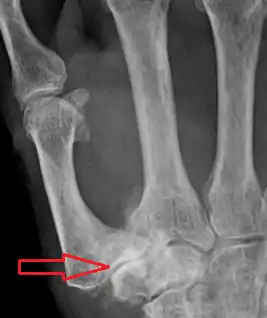

Dentro de las pruebas radiológicas, la que ofrece mayor fiabilidad para el diagnóstico de rizartrosis es la radiografía. Las formas de posicionamiento estándar de esta incluyen la vista postero-anterior, lateral y oblicua. Sin embargo, aunque estas posiciones permiten diagnosticar rizartrosis de forma fiable, ninguna de ellas permite evaluar la evolución de los cambios artrósicos en la articulación. La posición de Gedda, realizada mediante una rotación externa de la muñeca y la colocación de la mano en posición oblicua respecto a la placa radiográfica, permite una mayor fiabilidad a la hora de evaluar la situación del espacio intraarticular de la articulación trapeciometacarpiana, pero la dificultad a la hora de colocar la mano del paciente en esta posición hace que no se trate de un método estandarizado.[22][23][24]

La más utilizada es la clasificación de Eaton, basada en las características radiográficas de la articulación.